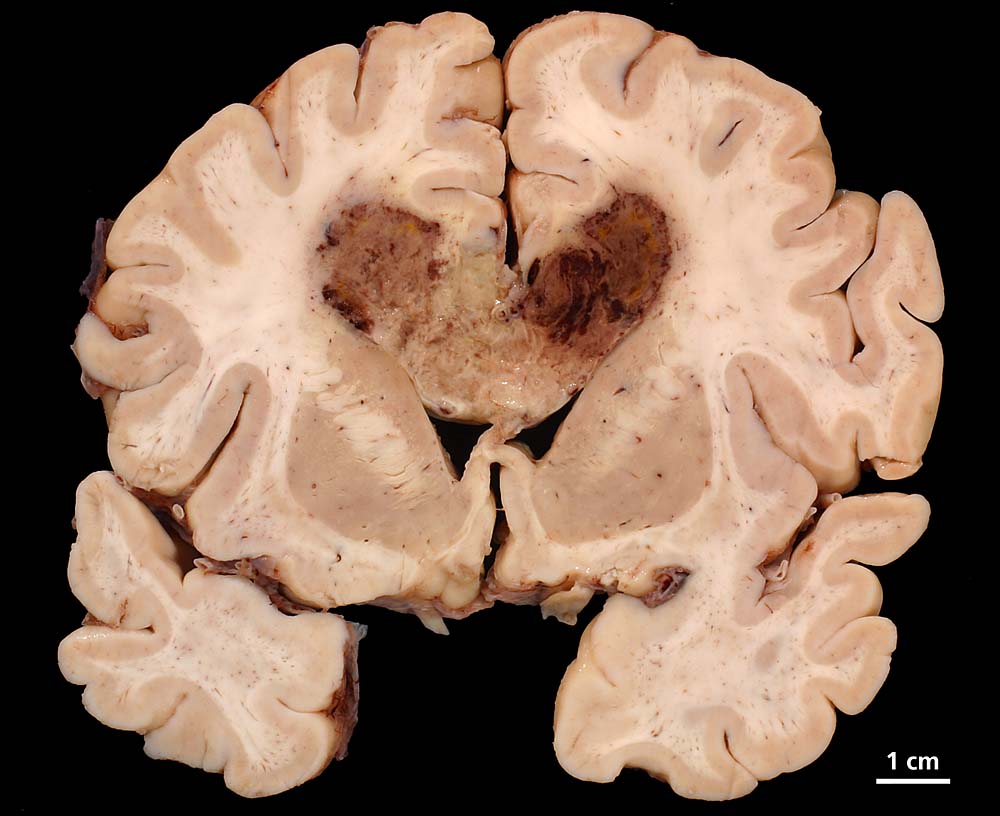

Lokalisation:

Bevorzugte Lokalisationen sind das Marklager des Frontal- und Temporallappens. Glioblastome des Hirnstammes sind selten und betreffen meist Kinder. Von dort breiten sie sich oft über den Balken schmetterlingsförmig auf die Gegenseite aus. Weniger als 5% der Tumoren wachsen multizentrisch. Eine Aussaat in den Subarachnoidalraum mit Metastasierung über den Liquor findet sich selten. Noch rarer sind hämatogene Metastasen in extraneurale Organe.

Morphologie:

Die Schnittfläche ist auffallend bunt. Dies ist bedingt durch ein Nebeneinander von graurotem vitalem Tumorgewebe, gelben Nekrosen, roten Einblutungen und gelegentlich grünlichen Gallertzysten.

Makroskopie